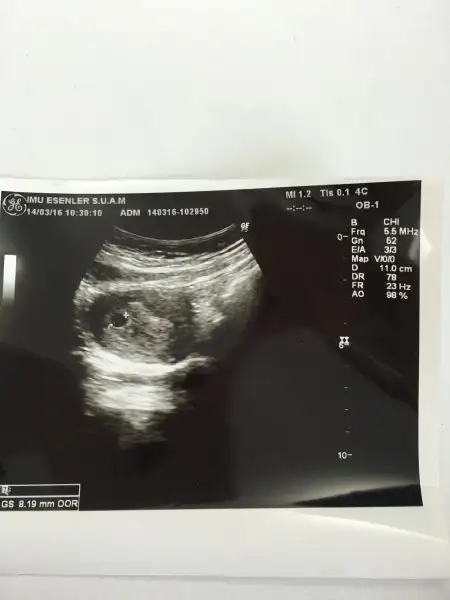

AY NE GÜZEL OLUURR HEP İSTEMİŞİMDİR BABANNEM İKİZ BENİM AMA BENİM KESE 8.19 MMDİ PAZARTESİ GÜNÜ PAZAR TEKRAR GİTMEYİ DÜŞÜNÜYORUM

CANIM EKTE GÖREBİLİRSİN KESE GÖRÜNTÜSÜNÜ BEN 4 MARTTA İLK HCG YAPTIM 315 PAZAR 605 SALI 1600 PERŞEMBE 3800 SONRA Bİ DAHA HCG YAPMADIM AMA BU ARTIŞLARA GÖRE PAZARTESİ 14 BİN CİVARI AY KEŞKE OLSA ÖYLE BİŞEY

Eklentiler

• image.webp

image.webp

10,4 KB · Görüntüleme: 70